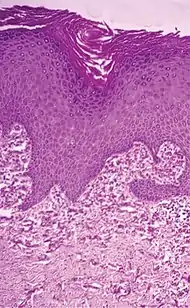

المُران هو تراكم الإيلاستين في الأنسجة، وهو شكل من أشكال الأمراض التنكسية. هناك العديد من الأسباب، ولكن السبب الأكثر شيوعًا هو تنكس النسيج المرن السفعي، المعروف أيضًا باسم تنكس النسيج المرن الشمسي، والذي ينتج عن التعرض الطويل والمفرط للشمس، وهي عملية تعرف باسم الشيخوخة الضوئية. تشمل الأسباب غير الشائعة للإصابة بالمران الجلدي: تنكس النسيج المرن الساعي الثاقب، والمرن التكلسي الثاقب والمرن البؤري الخطي.

| تنكس النسيج المرن السفعي | يحل الإيلاستين محل ألياف الكولاجين في الأدمة الحليمية والأدمة الشبكية | ![]() |